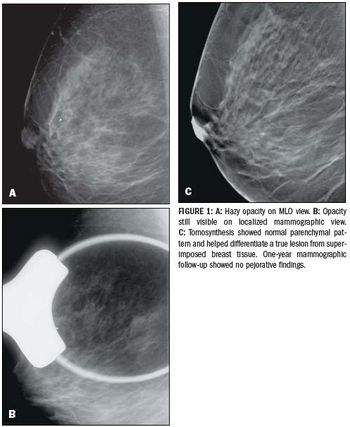

Digital breast tomosynthesis plus mammography provides a 40 percent reduction in patient recalls, reducing anxiety and potentially cutting cost and overall radiation dose.

Radiation doses from digital breast tomosynthesis is comparable to and could be lower than conventional two-view full-field digital mammography.